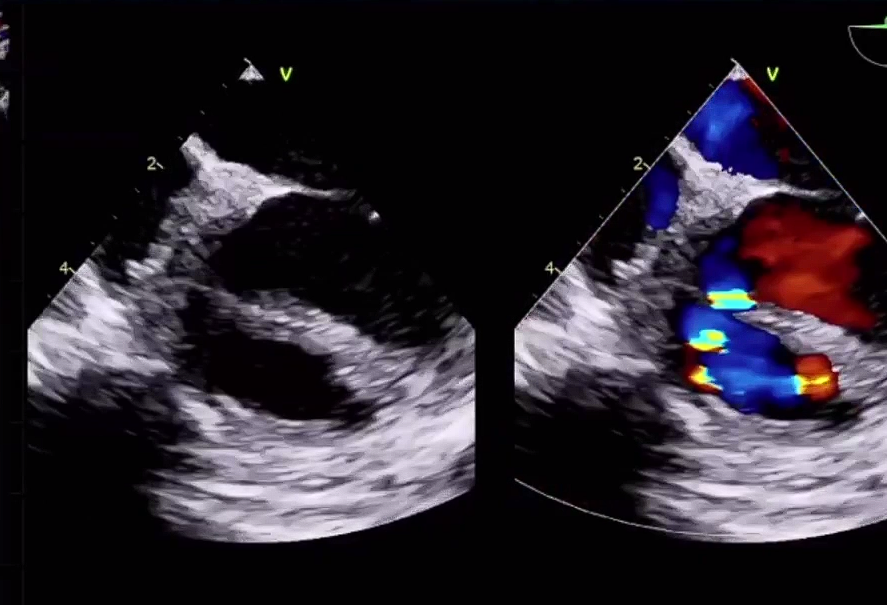

该例手术患者是4岁男性患儿,术前经胸超声检查示室间隔缺损4mm,室水平左向右高速分流。术者团队综合评估后,决定使用全降解封堵器行室间隔缺损的封堵。

▲术前超声